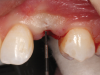

(56.) The provisional restoration was delivered and tightened to 15 Ncm while applying counter torque. Note that there is no pressure on the surrounding tissues and that the gingival embrasures were left open to allow for maximum incisal migration of the gingiva and papillae. The palatal and incisal surfaces were evaluated and modified to ensure that there was no contact throughout the excursive range.

Figure 56